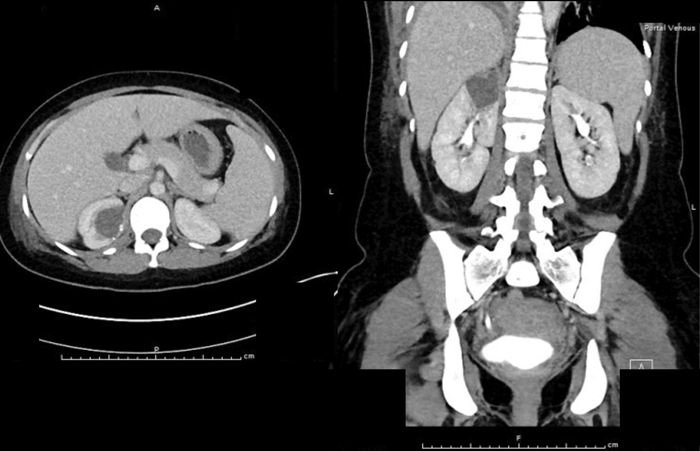

A 34-year-old lady is referred from the medics with right-sided loin pain and urosepsis. An initial ultrasound scan was arranged, followed by a subsequent CT scan. These scans did not show any renal / ureteric stone, but selected images are shown to the left.

- What do the images show?

A well-defined cystic structure in the upper pole of the right kidney. The cystic structure had calcification within the wall. CT demonstrated a fluid density mass within the cyst, with an irregular coarse foci of wall calcification. There is a solitary gas locule within the superior aspect of the cyst.